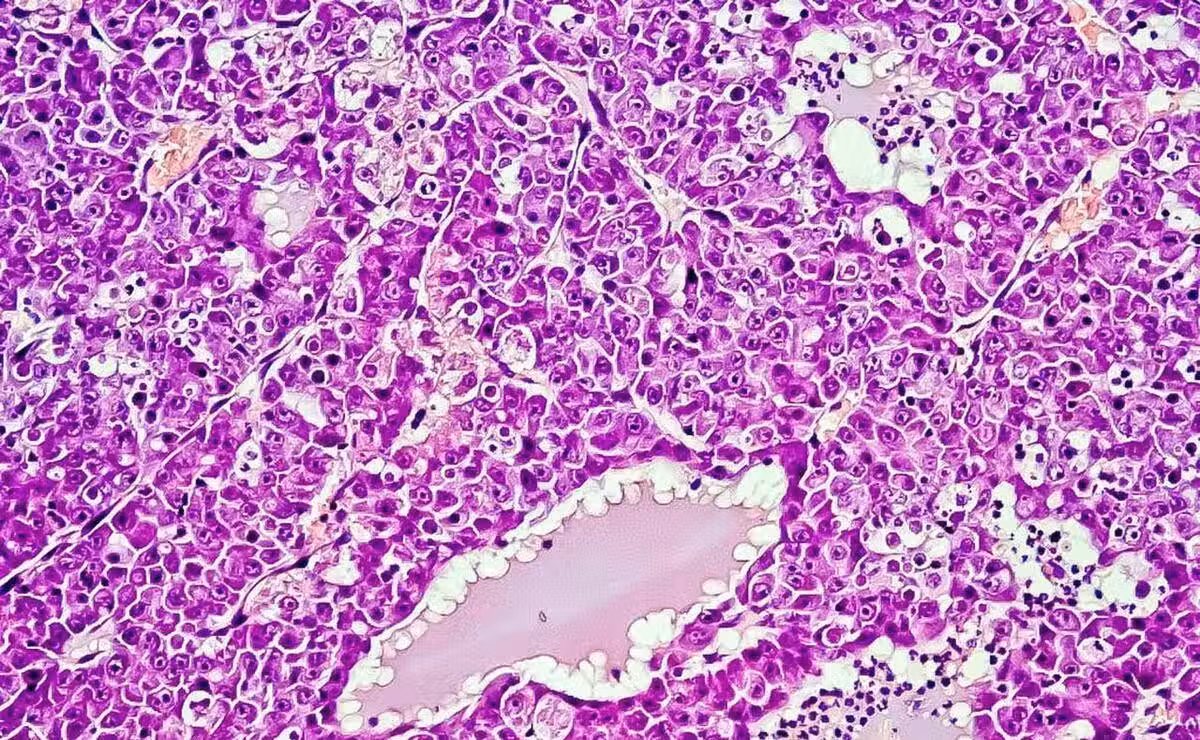

肝穿刺活檢:對於疑似肝癌的病灶,肝穿刺活檢可以通過取得組織樣本進行病理學檢查確認是否存在肝癌細胞的存在。